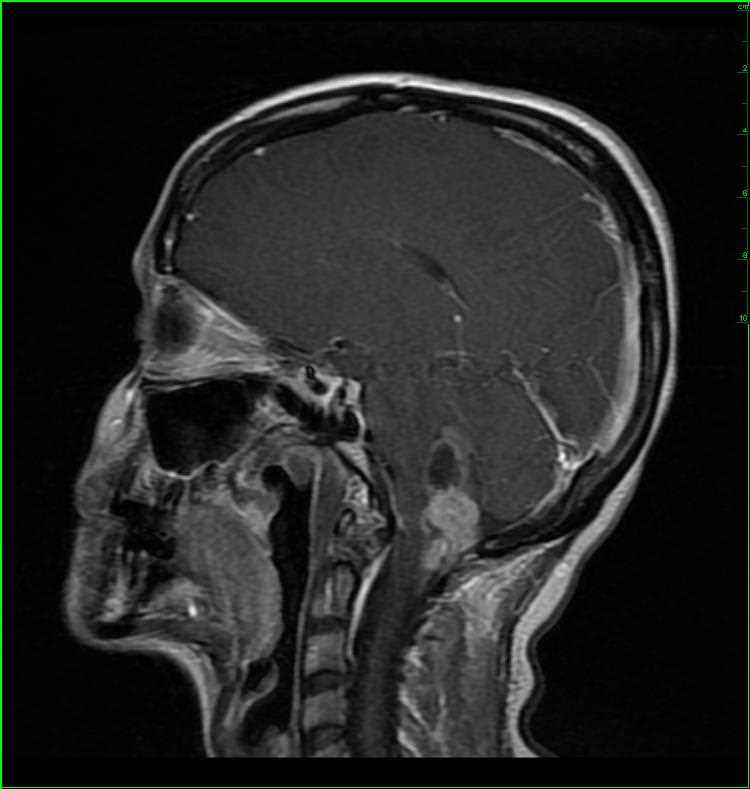

45-year-old female with chronic headaches. There is a well circumscribed, solid and cystic, T1-hypointense, T2/FLAIR-hyperintense, enhancing mass with increased blood volume centered on the foramen of Magendie. The mass enlarges the foramen spilling into both the cisterna magna and fourth ventricle. The differential includes ependymoma, subependymoma, choroid plexus papilloma, meningioma and metastatic disease, given the patients age. This was an anaplastic ependymoma. Ependymomas represent slow growing tumors of the ependymal cells. 2/3 are infratentorial with most centered in the fourth ventricle. Calcifications are common, and cysts and/or hemorrhage may be present. Despite the tumor having low cellularity, ADC values are typically low.